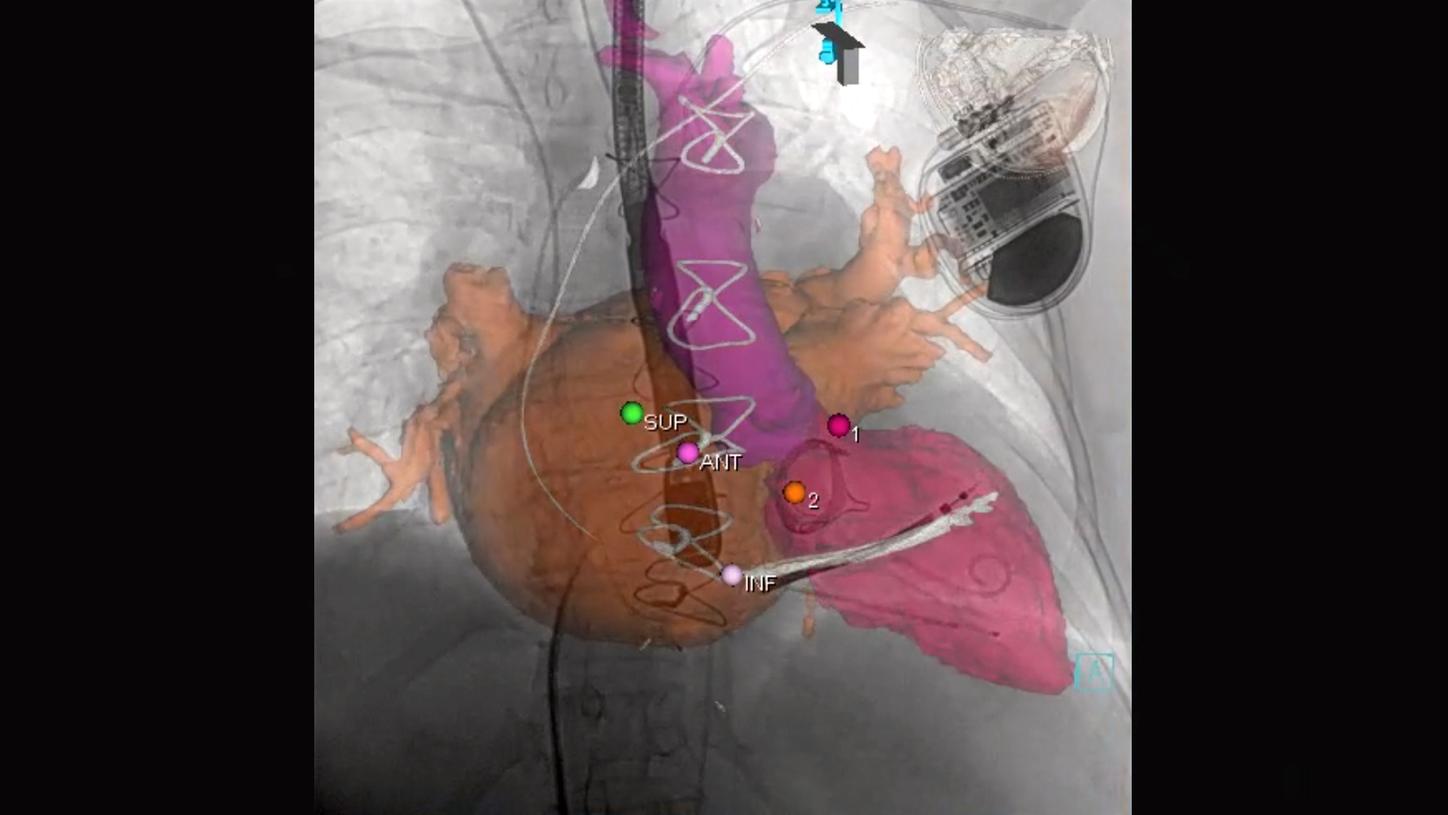

Precise system movements

Precision is key to improve the workflow in complex procedures. The reuse of vessel maps for DSA and 3D Roadmap even after C-arm and table movements speeds up the intervention and reduces dose and use of contrast media. ARTIS icono supports this with a (re)positioning accuracy of better than 0.5 mm.